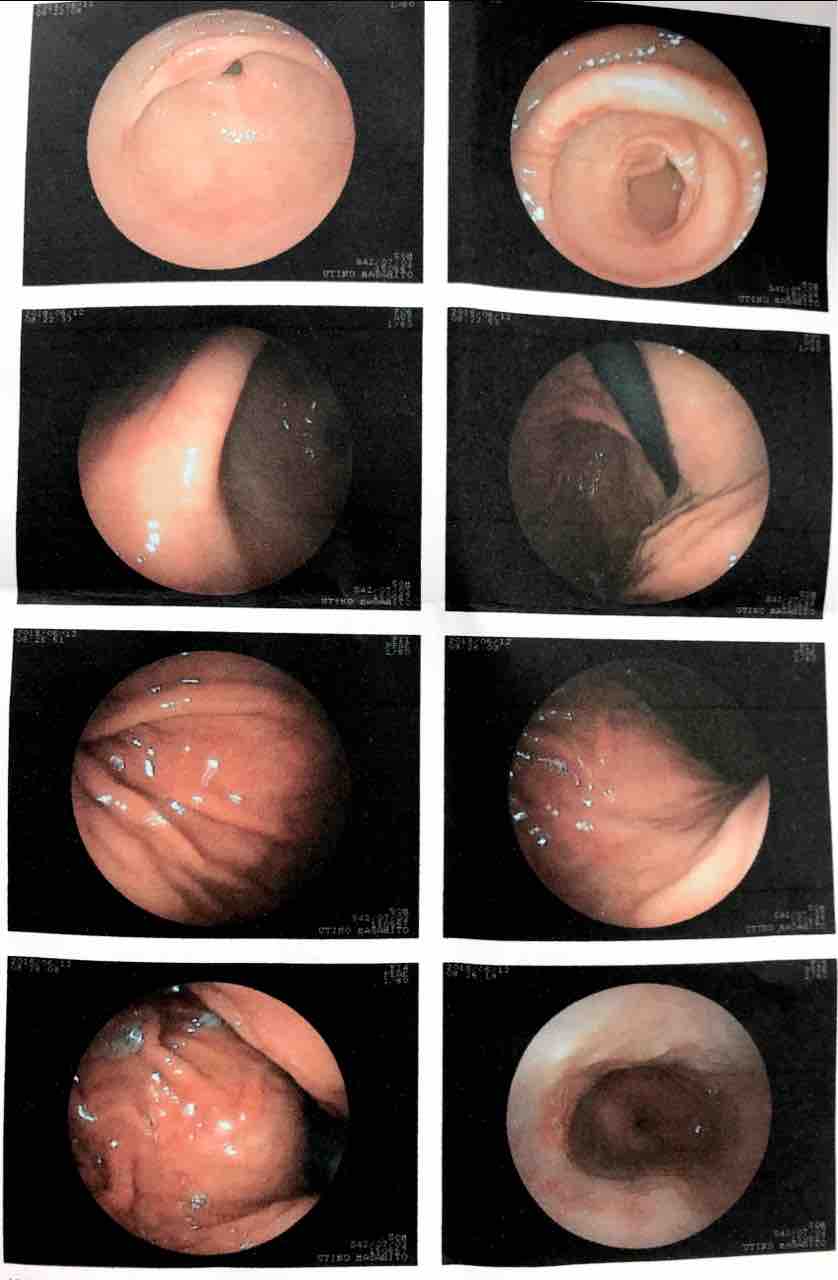

昨日の朝1番で、胃カメラをガッツリ飲んで来ました😵

7年ぶりの胃カメラは、かなりの細身になってました

ひと昔前より細身のカメラを左鼻からガッツリ差し込んで、昔からお世話になっとる先生が説明を始めます😅

「はい、奥まで入ったで画面見てみ」

「十二指腸も綺麗やぞ」

「よし胃に戻って〜」

「しっかり胃を見てみるでな〜😁」

「うん!胃も隅々まで綺麗や!」

「これなら何も心配ないぞ」

って言ってもらえて検査終了!

今やで淡々と語れるけど、この検査終了までの長い事長い事😵

幾らカメラが細身になったとは言え、鼻からカメラは結構苦痛です😂

全く問題無しの太鼓判をもらいました😆